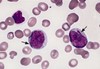

Smudge cells

CLL

Hairy Cell

= Hairy cell leukaemia